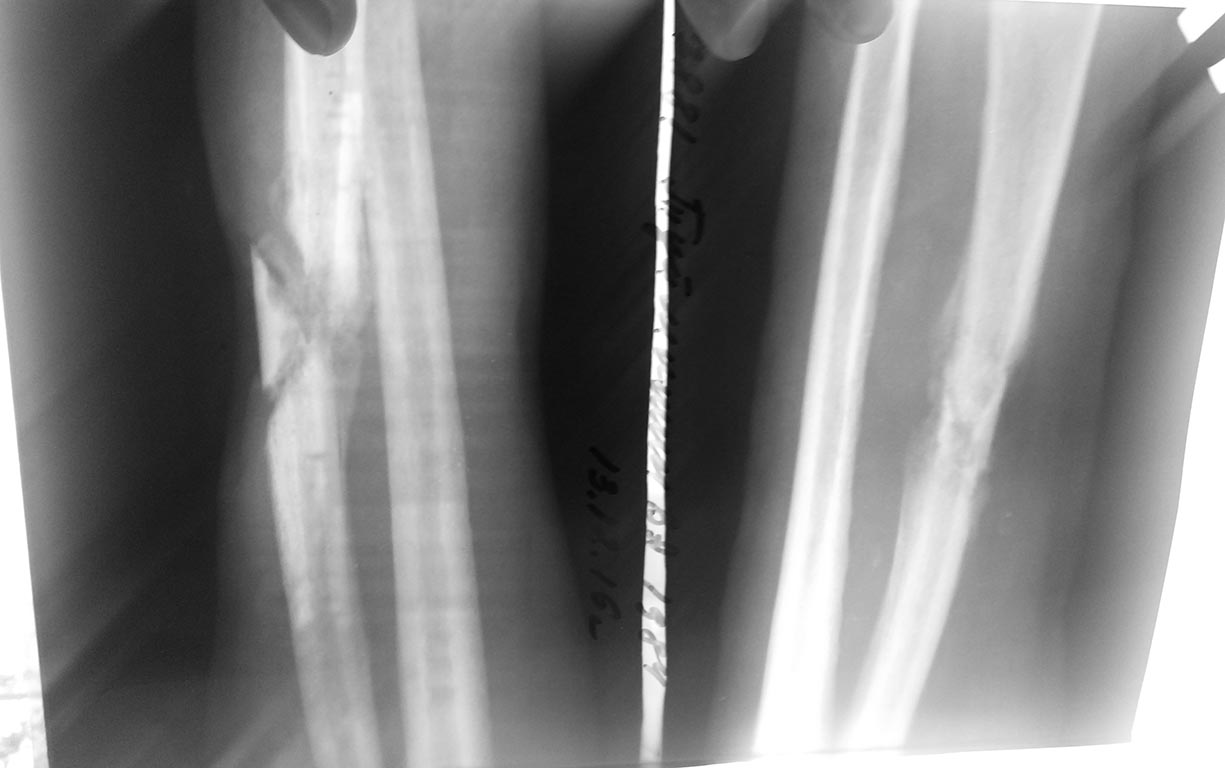

Больной 1984 г.р. 6 месяцев назад получил травму - удар высоковольтным

током.

Лечился сам. Обратился в районную больницу и был направлен с диагнозом:

инфицированная рана с/3 правго предплечья, остеомиелит лучевой кости.

Дефект кожи размером 3.0х3.0см, гнойное отделяемое.

Тактика лечения?

Резецировать концы отломков далее АВФ?